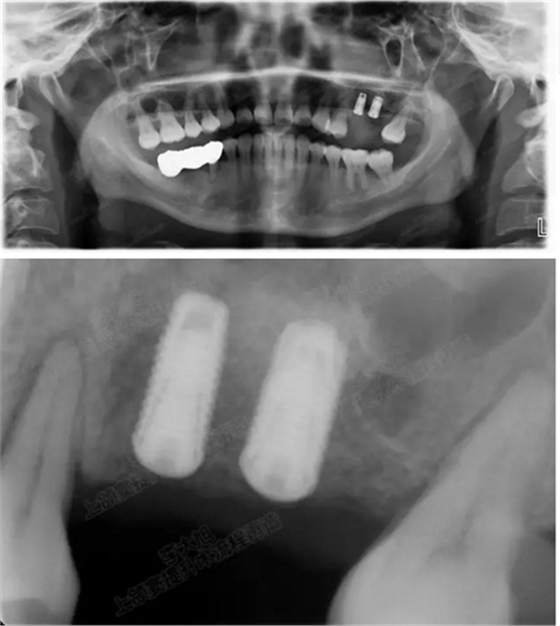

病例一

上頜竇多分隔3mm

05.png

提升8mm

06.png

07.png

修復(fù)時(shí)根尖片

08.png

09.png